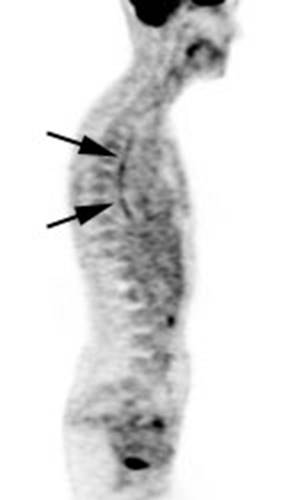

Figure 19 - Esophageal activity: The image below

demonstrates non-specific esophageal activity which appears as linear uptake

anterior to the spine (black arrows).